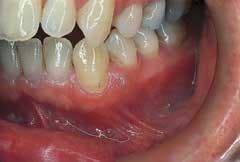

Intraoral examination revealed an elevated pinkish-translucent swelling on the attached gingiva between teeth #21 and #22 (see photo). The lesion appeared as a broad-based, compressible growth and measured approximately 0.5 centimeters in diameter. A smooth surface texture without ulceration or hemorrhage was noted. The teeth adjacent to the lesion were pulp tested for vitality and both teeth tested vital. Further examination of the oral soft tissues revealed no other masses present.

The gingival cyst of the adult is most often seen in individuals in the fifth and sixth decades of life. There is no sex predilection. The gingival cyst typically appears as a small, well-circumscribed swelling with a smooth surface texture. The lesion is broad-based. The color may be pale pink, translucent, or bluish. The gingival cyst is a slow-growing lesion and usually measures less than 0.5 centimeters in diameter. When palpated, the gingival cyst feels compressible. This lesion is asymptomatic.

The gingival cyst, as the name suggests, is found on the gingiva; the attached gingiva, free gingival margin, or interdental papilla areas may be involved. The gingiva of the mandible is involved more often than the maxilla, and the facial gingiva is more frequently involved than the lingual areas. In 60 to 75 percent of cases, the mandibular canine-premolar region is the area most often involved.